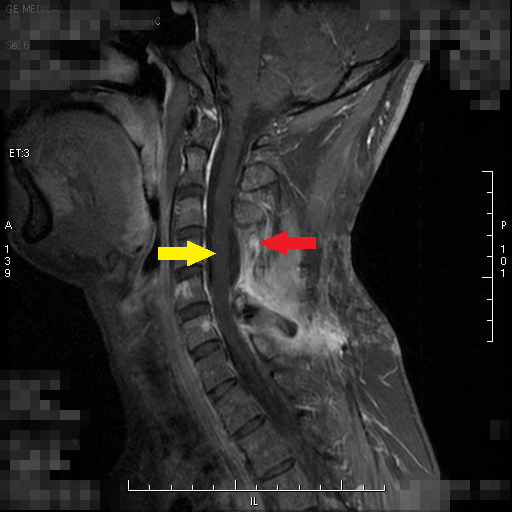

患者小康(化名)今年26岁,2013年查出椎管内肿瘤并进行切除,2015年12月复发来我院就诊,经神经外科医师评估后再次行切除术,病理报告为间变型血管周细胞瘤。术后三个月复查,核磁共振扫描提示:C5-C6(“C”代表颈椎)水平椎管内硬膜外左侧及C5/6左侧椎间孔区仍可见实性强化影,考虑为肿瘤病变,建议行术后放射治疗。

红色箭头所指的为病变,黄色箭头为脊髓

放疗科接诊后发现,小康的病变位置紧邻脊髓,常规放疗(X射线)容易造成脊髓受照超量,一旦超量,会导致神经系统严重并发症,放疗科医师建议小康行质子治疗。经与患者沟通后,联系台湾林口长庚质子中心医师进行远程会诊,并由台湾林口长庚纪念医院国际医疗中心个案管理师接管小康,全程协调安排其接受质子治疗。在台治疗结束后,小康回京定期到北京清华长庚医院复查、随访,目前状况良好,暂未发现肿瘤异常。